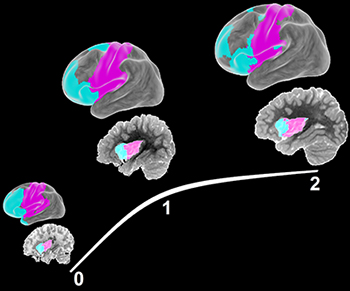

| Longitudinal development of insula functional specialization and associated network structure during infancy. |

By longitudinally following typically developing infants throughout the first years of life, we have studied the normal early brain development process using leading-edge resting-state fMRI (rsfMRI) imaging techniques and infant-specific behavioral testing strategies. Quantitative delineation of the developmental trajectories of different functional brain networks during infancy was extremely challenging until the advent of the rsfMRI technique, which can image infant brain functional organization during natural sleep. Using this advanced technology, we have documented the emergence and evolution of various functional networks during the first years of life. Our findings revealed significant local functional specialization, long-distance functional integration, and whole brain system optimization during normal brain development within this critical period. Overall, the normative functional development trajectories at different levels are characterized by a nonlinear trend featuring the most dramatic growth during the first year. These studies pave the way for study of abnormal development associated with genetic/environmental risks or brain disorders.